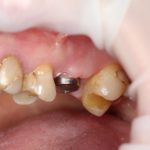

В общем, так и получилось. Уж не помню, почему я наобещал пациентке, что мы поставим ей имплантаты одновременно с остеопластикой. Но я наобещал. И, когда увидел клиническую картину в полости рта:

у меня появились серьезные сомнения, смогу ли я выполнить своё обещание. Вот только не спрашивай меня «Вот чо, сложно было по КЛКТ посмотреть?». Я же не спрашиваю тебя, где ты был в 2013 году, и сделал ли ты домашку. Но, в целом, план операции у нас не поменялся. Как и было оговорено, мы проведем остеопластику с одновременной имплантацией в боковом участке нижней челюсти справа.

Кстати, обрати внимание на ширину альвеолярного гребня (левая картинка). Она чуть меньше 3 мм. Это объясняет, почему я засомневался в возможности установки имплантатов одновременно с остеопластикой. Понятно и без КЛКТ.